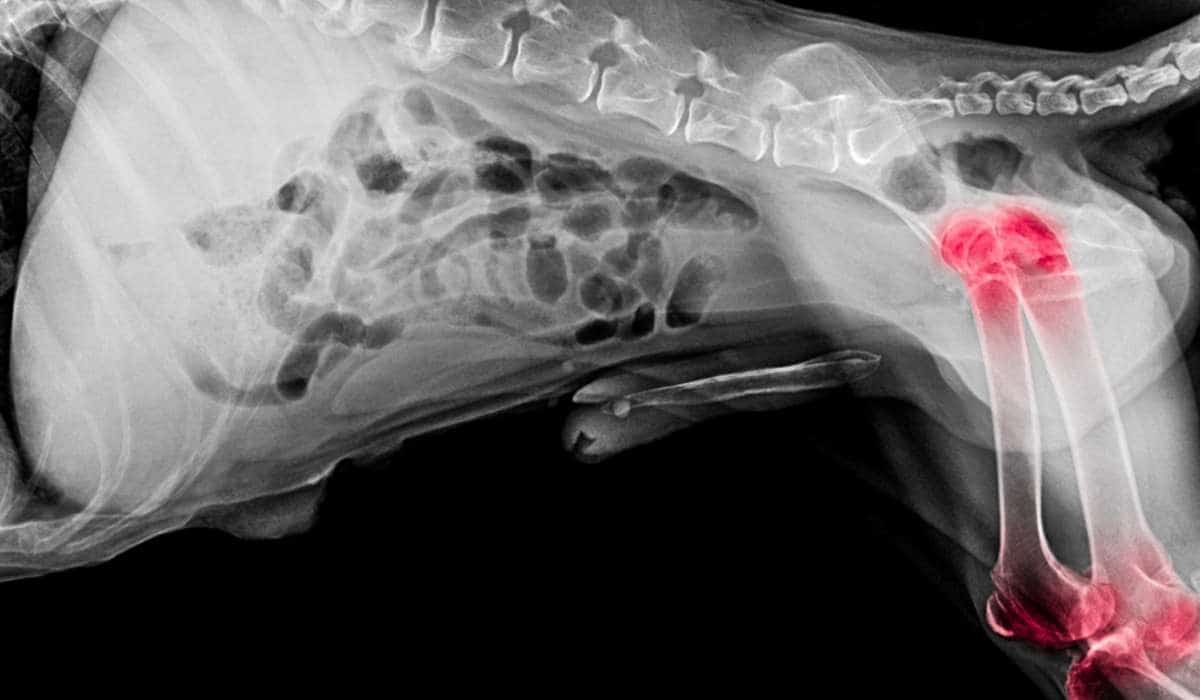

Displasia de cadera

La displasia de cadera es el mal desarrollo de las articulaciones de la cadera, lo que hace que la parte superior del hueso del muslo se asiente y se mueva de forma incorrecta en la cavidad de la cadera.

Con el tiempo, la displasia de cadera conduce a una dolorosa artritis.

La displasia de cadera es un problema común en los labradores y los schnauzers, por lo que todos los perros de cría deben ser evaluados por un veterinario antes del apareamiento.

El veterinario evaluará la salud de las caderas del perro y su criador estará encantado de comunicarle estos resultados.